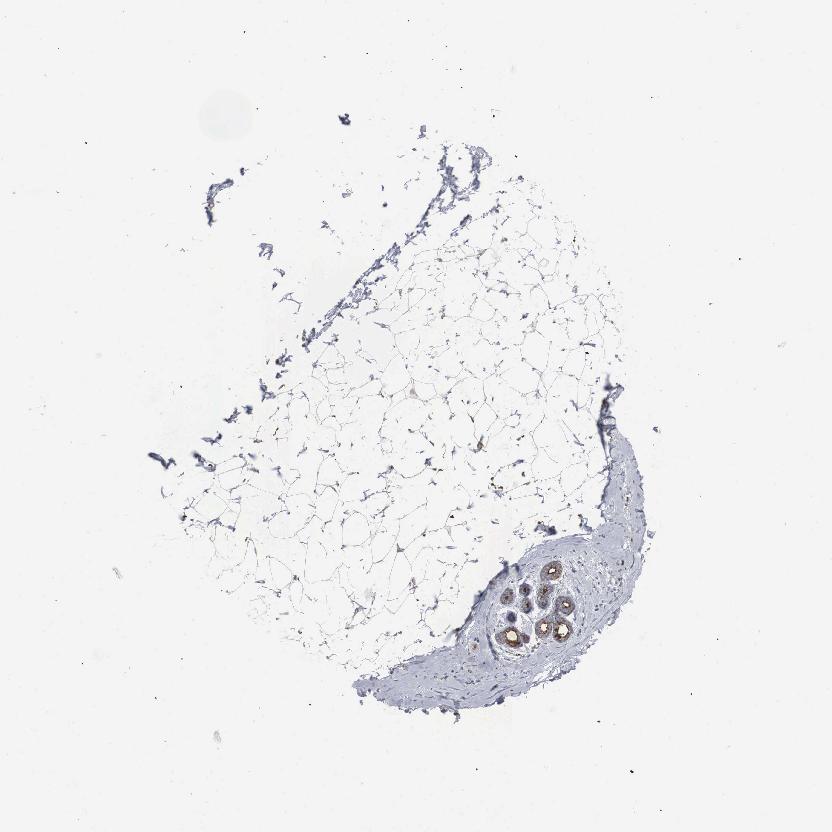

SOFT TISSUE 1 - Antibody stainingi

Antibody staining in the annotated cell types in the current human tissue is reported as not detected, low, medium, or high, based on conventional immunohistochemistry profiling in selected tissues. This score is based on the combination of the staining intensity and fraction of stained cells.

Each image is clickable and will lead to virtual microscopy that enables deeper exploration of all samples and also displays staining intensity scores, fraction scores and subcellular localization as well as patient and tissue information for each sample.

Antibody HPA000410Antibody HPA000554

Chondrocytes Not detectedNot detected

Fibroblasts Not detectedNot detected

Peripheral nerve Not detected-

SOFT TISSUE 2 - Antibody stainingi

Chondrocytes Not detected-

Peripheral nerve Not detectedLow